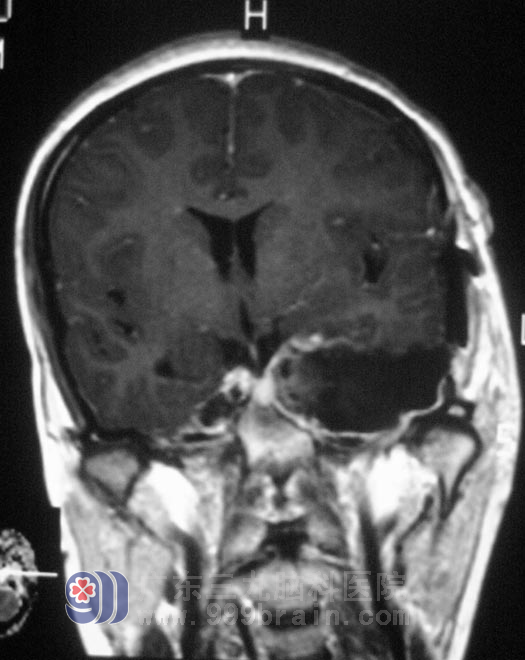

8月16日由鲁明主任主刀,在全麻下行左侧中后颅窝占位切除术,术中见肿瘤呈灰白色,外上方有三叉神经粘连,后侧达脑干,血供丰富,质地较韧,与周围组织轻微粘连,在显微镜下予肿瘤分块,成功全切除。术后病理:(左侧鞍旁)神经鞘瘤。经过治疗,出院时的倩倩,笑容已恢复了往日的甜美。